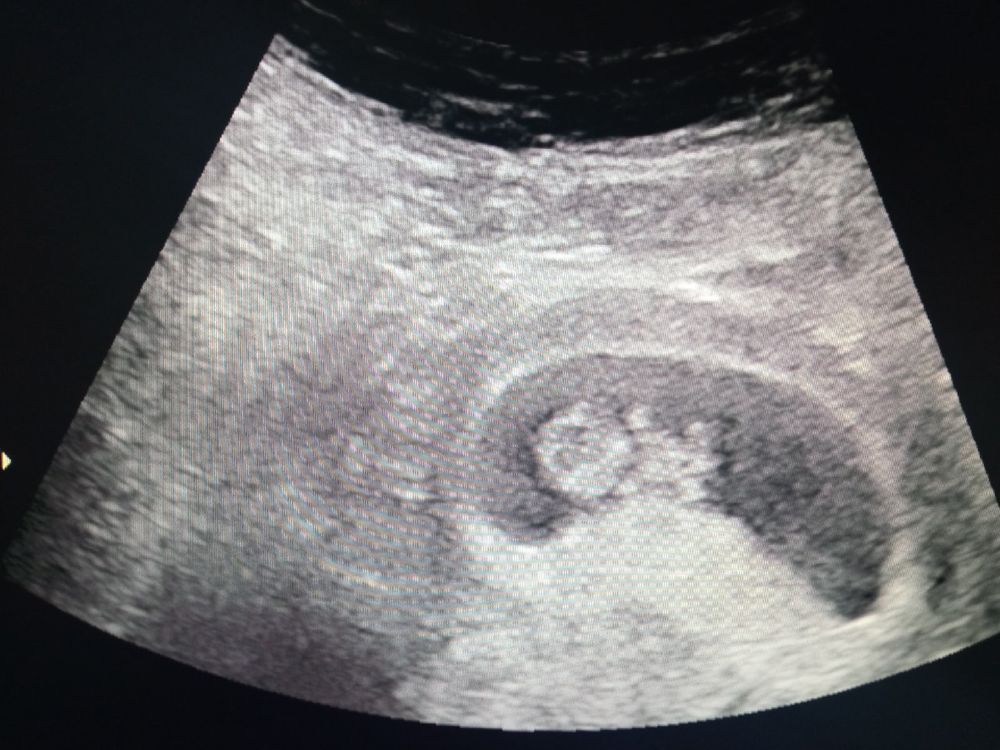

9-10 неделя

Пол, мальчик? Помогите разобраться в КТГ